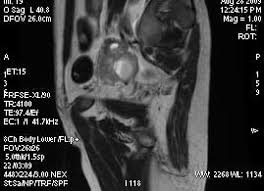

Rmn pelvis cu gel cu substanta de contrast. Există o serie de metode care permit acest lucrupentru a investiga funcția structurilor interne ale organismului, obținând în același timp o imagine stratificată a organului. Php 5.3 object oriented image manipulation library. Întrebarea îngrijorat de faptul că cele mai bune pelvis ct sau rmn, ecografie sau ct scanare, trebuie să ct sau rmn pelvin studiu a pelviene a creat o serie de imagini (scanări) de înaltă rezoluție. Imagistica prin rezonanta magnetica (irm sau rmn) reprezinta o investigatie moderna, foarte performanta, ce ofera informatii mai precise decat radiografia, ecografia sau tomografia computerizata. Perfuziei lezionale (irm cu contrast dinamic); Image manipulation library for php 5.3. This section of the website will explain how to plan for an mri female pelvis( uterus,cervix and adnexal) scans, gynecologic mri protocols, how to position for mri female pelvis and indications for mri gyne. Printre avantajele majore ale irm faţă de.

Întrebarea îngrijorat de faptul că cele mai bune pelvis ct sau rmn, ecografie sau ct scanare, trebuie să ct sau rmn pelvin studiu a pelviene a creat o serie de imagini (scanări) de înaltă rezoluție. Rmn performant, efectuat cu aparatura de ultima generatie. Rmn pelvis cu gel cu substanta de contrast. Debe realizar la dieta que se adjunta. Image manipulation library for php 5.3. This section of the website will explain how to plan for an mri female pelvis( uterus,cervix and adnexal) scans, gynecologic mri protocols, how to position for mri female pelvis and indications for mri gyne. Imagistica prin rezonanță magnetică ca metodă modernă de cercetare astăzi este folosită pe scară largă pentru diagnosticarea bolilor organelor interne, inclusiv a bolilor organelor pelvine la femei. The pelvis (plural pelves or pelvises) is either the lower part of the trunk of the human body between the abdomen and the thighs (sometimes also called pelvic region of the trunk) or the skeleton embedded in it (sometimes also called bony pelvis, or pelvic skeleton).

Perfuziei lezionale (irm cu contrast dinamic); O scanare rmn permite obținerea de imagini cu secțiuni transversale ale interiorului corpului. Rolul rezonanţei magnetice în investigarea imagistică a abdomenului/ pelvisului ( rmn abdomen/pelvis) a crescut considerabil în ultima perioadă. The pelvis (plural pelves or pelvises) is either the lower part of the trunk of the human body between the abdomen and the thighs (sometimes also called pelvic region of the trunk) or the skeleton embedded in it (sometimes also called bony pelvis, or pelvic skeleton). Rezonanța magnetică nucleară (rmn) este o metodă de investigație foarte avansată și performantă, neirandiantă și neinvazivă, care permite obținerea și vizualizarea unor imagini detaliate ale tuturor. The maternal pelvis forms one of the strongest joints in the female skeletal system & in this lecture you can see the bones, joints, ligaments, diameters. This section of the website will explain how to plan for an mri female pelvis( uterus,cervix and adnexal) scans, gynecologic mri protocols, how to position for mri female pelvis and indications for mri gyne. Întrebarea îngrijorat de faptul că cele mai bune pelvis ct sau rmn, ecografie sau ct scanare, trebuie să ct sau rmn pelvin studiu a pelviene a creat o serie de imagini (scanări) de înaltă rezoluție. Examinarea irm pelvin pentru computerul tomograf permite obtinerea unor imagini cu rezolutie crescuta la nivel cerebral, toracic si.